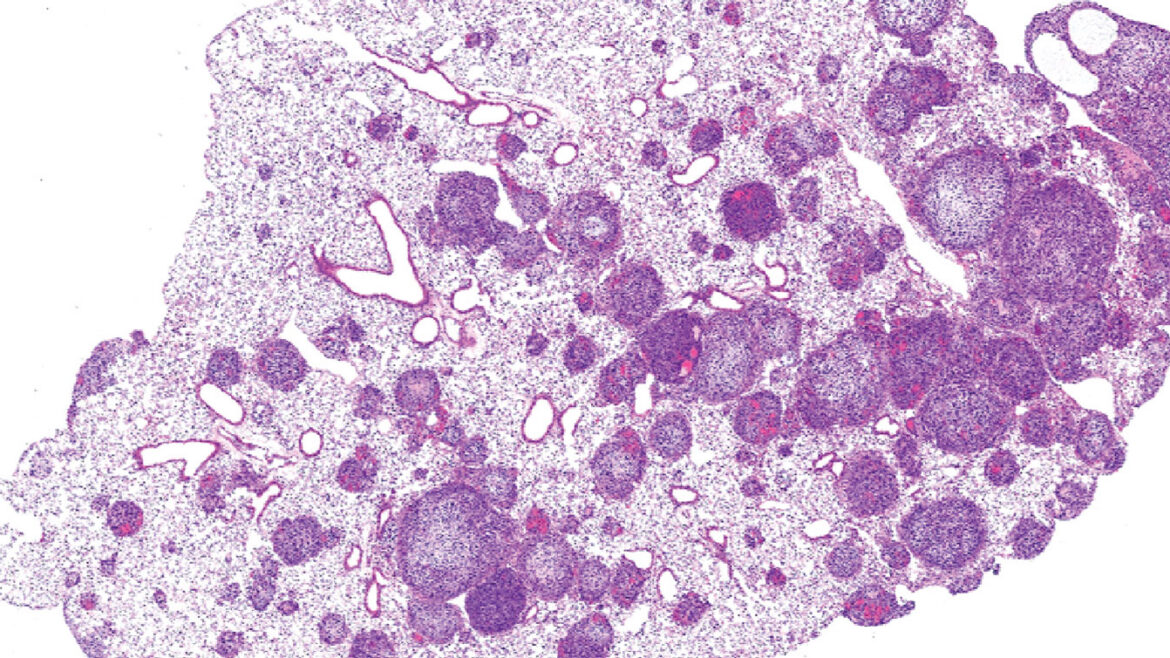

Speeding Up Science With Patient-Derived Xenografts https://pediatricsnationwide.org/wp-content/uploads/2026/04/Nintedanib-Lungs_Intro-Art-header-1024x483.jpg 1024 483 Katie Brind'Amour, PhD, MS, CHES https://pediatricsnationwide.org/wp-content/uploads/2021/03/Katie-B-portrait.gifA perfect storm of advanced technologies and scientific collaboration opens doors to rapid progress in pediatric oncology research. The world of pediatric cancer research faces the challenges of small patient numbers, increased ethical considerations, limited funding and poorly classified diseases. In some ways, these challenges reflect the field’s successes over the past half century, which…